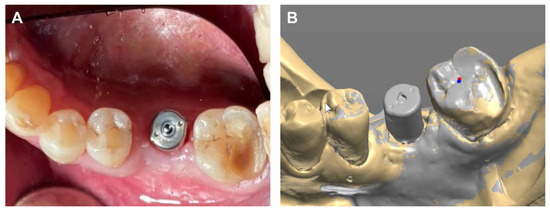

After the height of the multi-abutments with gingival gauge was determined, the multi-abutments were connected to the osseointegrated implant fixture with a tightening torque of 35 N/cm2 (Figure 9A). Next, healing caps were connected to the multi-abutments (Figure 9B). The final impressions were taken using an addition-type silicone impression material (Aquasil LV and XLV; Dentsply Sirona, Milford, DE, USA).

Next, the same laboratory process described in case 1 was performed. The prosthesis was designed on the CAD software, and a prefabricated link was selected through the scan data obtained from the model scan (Figure 10). A final prosthesis was obtained by milling zirconia through a CAM milling machine. A prefabricated substructure (link) (Toplan Co., Seoul, Republic of Korea) was fitted to the final prosthesis through frictional force.

Figure 9. (A) Multi-abutment connection, (B) Healing cap connection.

Figure 10. Prosthetic design of implant prosthesis on CAD software program.